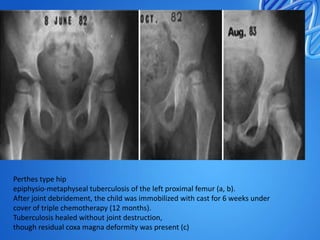

Perthes type hip

epiphysio-metaphyseal tuberculosis of the left proximal femur (a, b).

After joint debridement, the child was immobilized with cast for 6 weeks under

cover of triple chemotherapy (12 months).

Tuberculosis healed without joint destruction,

though residual coxa magna deformity was present (c)

Perthes type hip epiphysio-metaphysealtuberculosis of the left proximal femur (a, b). After joint debridement, the child was immobilized with cast for 6 weeks under cover of triple chemotherapy (12 months). Tuberculosis healed without joint destruction, though residual coxa magna deformity was present (c)